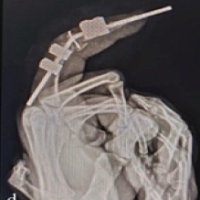

After resuscitation of the patient on presentation in accordance with advanced trauma life support protocol, the management involved emergent reduction, stabilization, and assessment of lower limb perfusion, followed by routine investigations. X-rays were taken in two planes: Anteroposterior and lateral views. In case of suspected vascular injury, an ultrasound Doppler scan followed by computed tomography angiography was done after stabilization of the limb. Patients were admitted post-reduction for a period of at least 7 days for monitoring and assessment of vascular status and prophylactic administration of low-molecular-weight heparin injection, irrespective of whether they were to be operated upon or not.